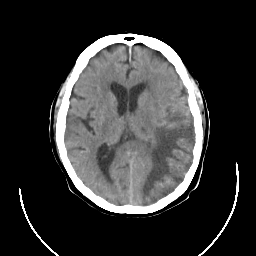

CT Study #3 -- Slice #15

Tour 1: Next/Previous/Start: In this slice, the lesion extends from near the occipital pole to the Sylvian fissure, conforming to the territory of the posterior branch of the middle cerebral artery.

[Home][Help][Clinical][Tour 1] Slice 15